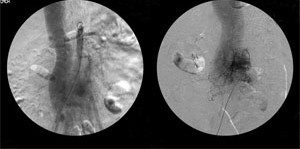

对患者进一步行腹主动脉血管造影(图3)检查,未发现肾血管狭窄现象,但检查中,显影剂注射入腹主动脉后,快速流向脊髓动脉而非肾动脉,并回到下腔静脉,显示患者动静脉畸形(AVM),将血液由脊髓动脉分流至下腔静脉,而此动静脉畸形范围包含整个下腹部。 该患者最后被确诊为腹主动脉动静脉畸形导致心衰而使肾血流减少。

图3 腹主动脉血管造影,在显影剂注入腹主动脉后,快速地流入脊髓动脉,接着流入下腔静脉, 肾动脉无明显狭窄。